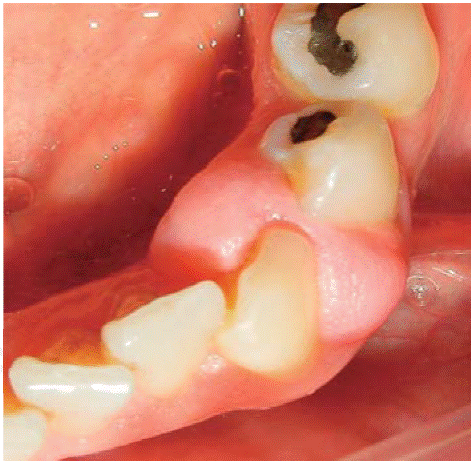

Paciente de género femenino, de 29 años de edad, sistémicamente sana, acude a consulta refiriendo presentar lesión gingival a nivel del sector anterior del maxilar superior hace tres años aproximadamente. Refiere también que la lesión apareció durante el periodo de gestación y fue creciendo progresivamente y sin presentar dolor. Al examen clínico se observa tumor pediculado, móvil, de consistencia blanda, de aproximadamente 20 X 16 mm, localizado a nivel de piezas 23 y 24, de color rosado con focos de queratinización (Figura 17). A la evaluación periodontal se encontraron bolsas periodontales y un índice de higiene oral (O'Leary) de 78%. Radiográficamente se aprecia cálculo interproximal en la zona de la lesión gingival (Figura 18).

Diagnóstico presuntivo: granuloma piógeno.